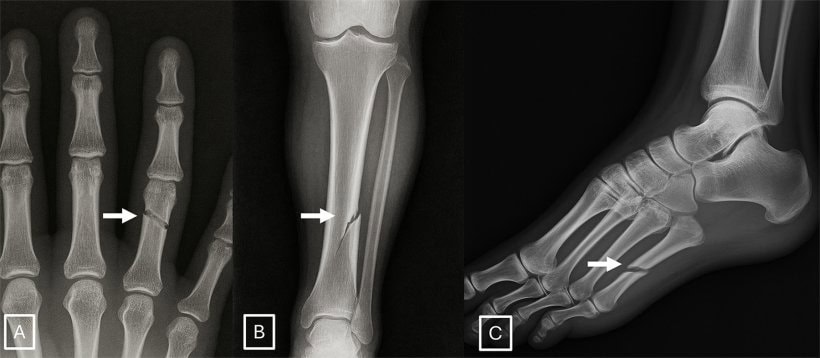

Yapay zekâ tartışması yeni bir eşiğe daha geldi. Bu kez mesele sadece fotoğraf, video ya da ses üretmesi değil. Son araştırmalara göre yapay zekâ, gerçeğine çok benzeyen sahte röntgen görüntüleri de üretebiliyor. Dahası, bu görüntüler bazı radyologları ve bazı yapay zekâ sistemlerini bile yanıltabiliyor.

Araştırmada 12 farklı merkezden, 6 ülkeden 17 radyolog yer aldı. Toplam 264 röntgen görüntüsü incelendi. Bu görüntülerin yarısı gerçekti, yarısı ise yapay zekâ ile üretilmişti. Radyologlar ilk aşamada, görüntülerin sahte olabileceği özellikle söylenmeden değerlendirme yaptı. Sonuç çarpıcıydı: Sahte görüntüleri doğru ayırt etme oranı yalnızca yüzde 41’de kaldı. Katılımcılara görüntüler arasında yapay zekâ ile üretilmiş olanlar da bulunduğu söylendiğinde bu oran yüzde 75’e çıktı. Yani uzmanlar uyarıldığında daha başarılı oldu ama ilk bakışta sahte görüntüler ciddi biçimde kafa karıştırdı.

Üstelik sorun sadece insanlar değil. Reuters’ın aktardığına göre GPT-4o, GPT-5, Gemini 2.5 Pro ve Llama 4 Maverick gibi gelişmiş sistemler de sahte röntgenleri ayırt etmede değişen oranlarda zorlandı. Bazı modeller daha iyi sonuç verdi, bazıları daha düşük doğrulukta kaldı. Bu da yapay zekânın, başka yapay zekâları bile yanıltabilecek kadar ikna edici tıbbi görüntüler üretebildiğini gösteriyor.

Buradaki asıl tehlike, kötüye kullanılma ihtimali. Araştırmacılar bu tür görüntülerin dolandırıcılık, yanlış teşhis, sahte hasta kaydı, sigorta suistimali ya da sağlık verisinin manipülasyonu gibi alanlarda kullanılabileceği uyarısında bulunuyor. Radyoloji gibi güvenin temel olduğu bir alanda, görüntünün gerçek olup olmadığından emin olamamak çok daha büyük bir sorunun kapısını açıyor. Bu yüzden çalışma aynı zamanda, sağlık sisteminde güvenlik ve doğrulama sorunu olarak görünüyor.

Araştırmanın bir başka dikkat çekici bulgusu da şu: Uzmanlık süresi her zaman koruma sağlamıyor. ScienceDaily’nin aktardığına göre radyologların yıllar içindeki deneyimi ile sahte görüntüleri yakalama başarısı arasında güçlü bir ilişki bulunmadı. Buna karşılık kas-iskelet alanında çalışan bazı radyologların daha iyi performans gösterdiği belirtildi. Yani tecrübeli bir doktorun, sahte röntgeni hemen anlayabileceği gibi bir bilgi çok da kanıtlanabilir bir gerçek değil.

Peki çözüm ne olabilir? Uzmanlar, tıbbi görüntülere görünmez filigranlar eklenmesi, cihazdan çıktığı anda kriptografik imza oluşturulması ve görüntülerin kaynağının teknik olarak doğrulanması gibi yöntemler öneriyor. Bir başka deyişle, yapay zekâ güçlendikçe sadece teşhis araçlarını değil, doğrulama mekanizmalarını da güçlendirmek gerekecek.

Kısacası yapay zekâ artık sadece sanatçıyı, yazarı ya da tasarımcıyı tedirgin etmiyor. Şimdi sağlık sisteminin en hassas alanlarından birine de dokunuyor. Röntgen gibi en temel görüntüleme araçlarında bile gerçeğe çok yakın sahteler üretilebiliyorsa, önümüzdeki dönemde asıl soru şu olacak: Gördüğümüz şey gerçekten bir hastaya mı ait, yoksa yapay zeka tarafından çok iyi üretilmiş sahte bir görüntü mü?